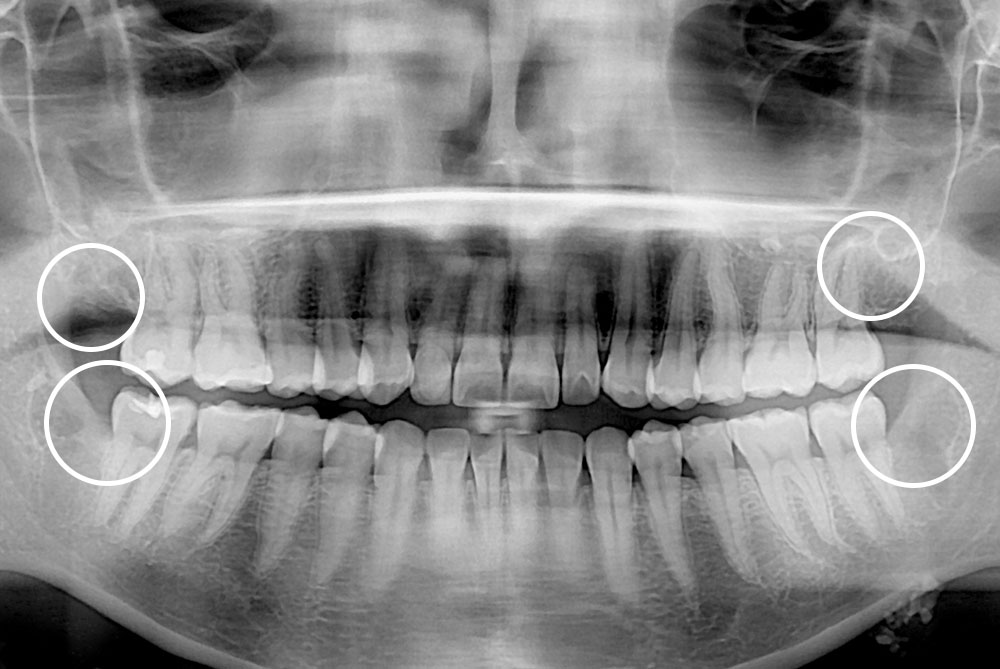

[사랑니] 매복 사랑니 발치

치료전 : 2018-11-02

세종치과는 구강악안면외과학 박사이신 원장님이 발치하는 치과입니다.